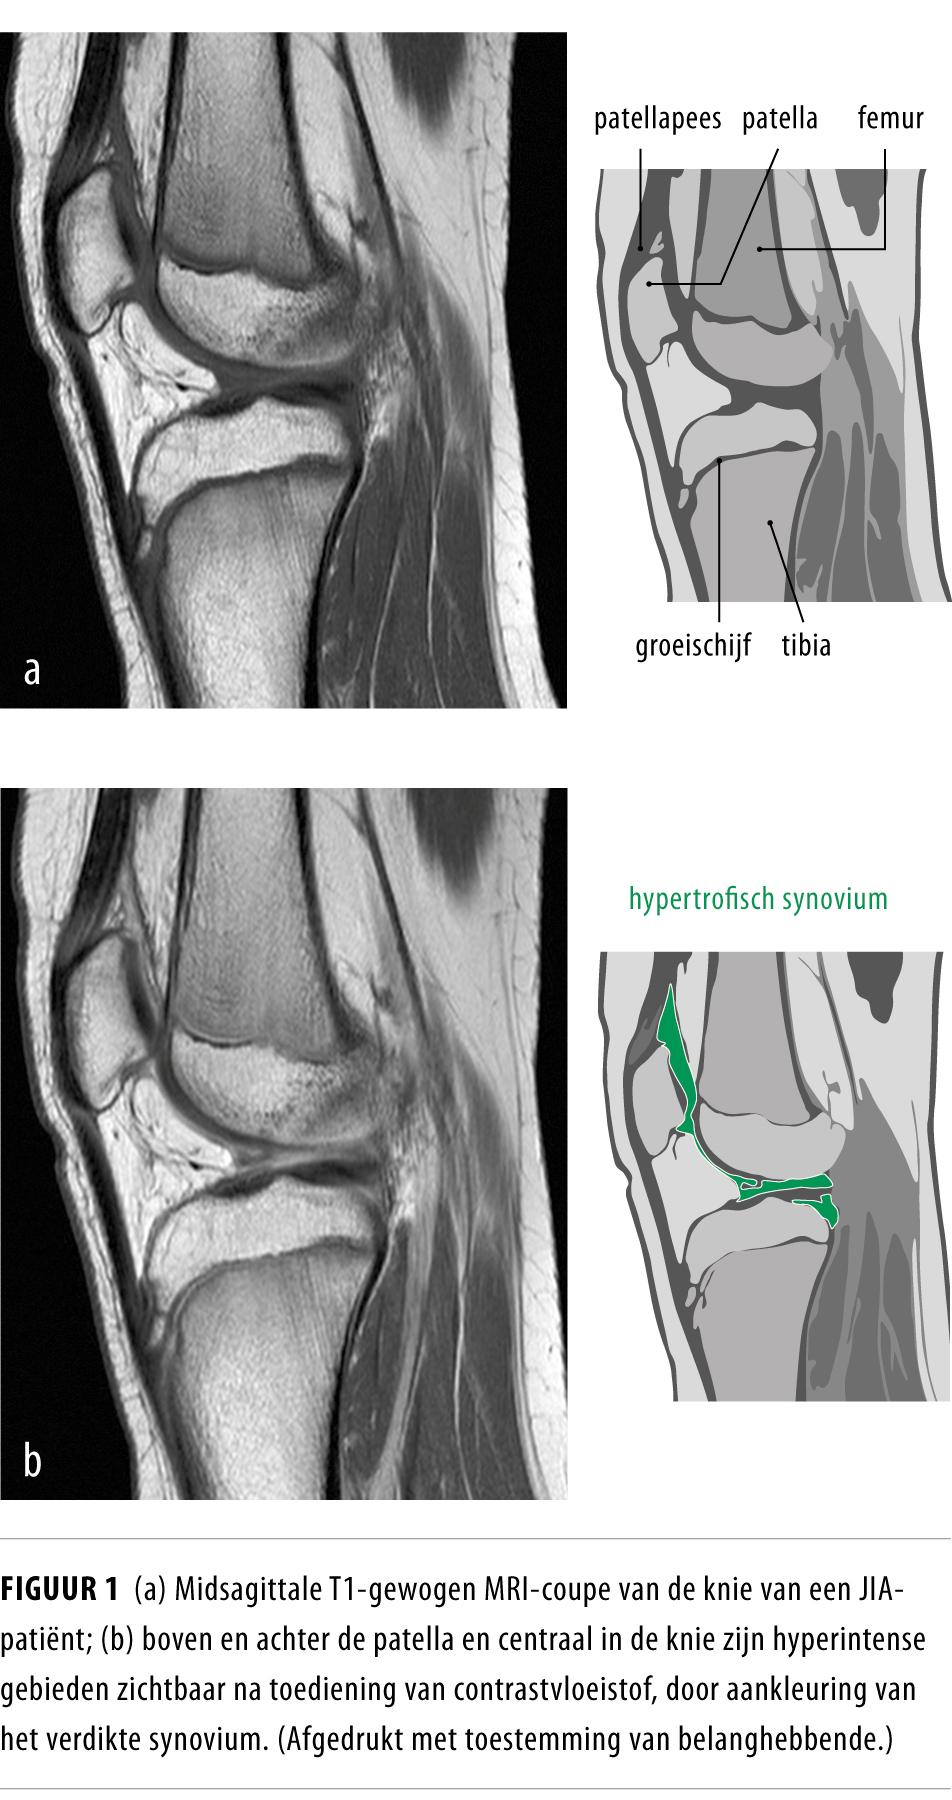

MRI heeft een hoge sensitiviteit voor de detectie van artritis in het kaakgewricht en in andere gewrichten die vaak aangedaan zijn (targetgewrichten).8 MRI met contrasttoediening maakt het mogelijk om ontstekingen van het synovium en peesschedes aan te tonen, en ook beenmergoedeem, boterosies en kraakbeenschade (figuur 1).16,17 MRI is de enige beeldvormende techniek die objectief en zonder stralenbelasting alle relevante structuren die een rol spelen bij JIA volledig en in meerdere richtingen kan afbeelden. MRI-onderzoek is daarom een goed hulpmiddel bij het stellen van de diagnose en bij het monitoren van ziekteactiviteit en therapierespons.16

Zowel met echografisch onderzoek als met MRI is subklinische synovitis aangetoond bij een aanzienlijk deel van de patiënten die klinisch geen tekenen van actieve ziekte hadden.16,17 Het klinisch belang van deze bevindingen is vooralsnog onduidelijk; mogelijk helpt het bij het inschatten van het risico op het opvlammen (‘flaring’) van de ziekte na minderen of stoppen van medicatie. Om vast te stellen wat precies de betekenis is van subklinische synovitis, is vergelijking nodig met echo’s en MRI-scans van gewrichten van niet-aangedane controlepersonen en zouden JIA-patiënten langdurig gevolgd moeten worden.